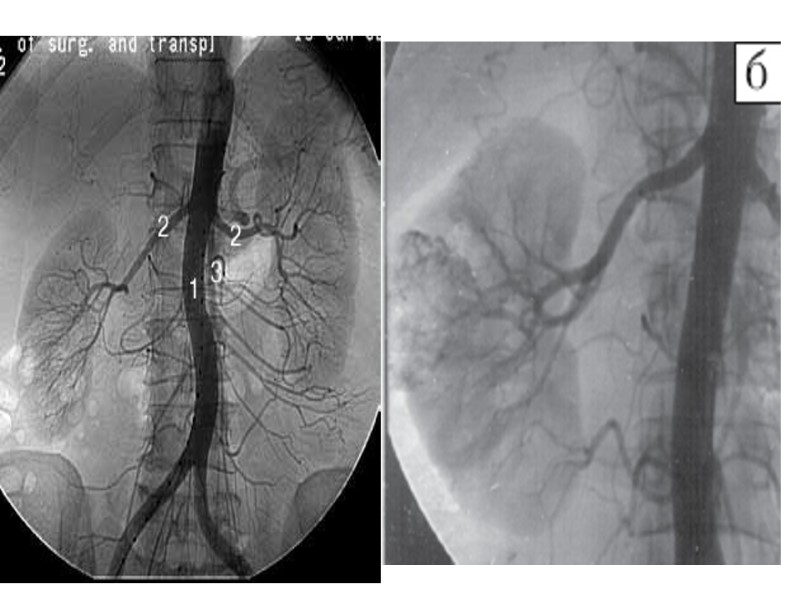

- Известен способ флебокавографии, когда катетер вводят в плечевую вену и затем через правое предсердие в нижнюю полую вену. Некоторые клиницисты применяют селективную катетеризацию почечной вены и селективную почечную флебографию (Dalla-Palma, Servello, 1956; Olsson, 1962). На почечных флебограммах удается выявить изменения, характерные для того или иного почечного заболевания: туберкулеза почки, гидронефроза, поликистоза и др. При сдавлении нижней полой вены опухолью почки или надпочечника либо конгломератом увеличенных лимфатических узлов (например, метастазами злокачественной опухоли яичка) на венокавограмме выявляются округлые или овальные дефекты наполнения полой вены, деформация или смещение ее (рис. 14, 15). Рис. 14. Венокавограмма. Мужчина 48 лет. Гипернефроидный рак правой почки. Сдавленно и смещение опухолью нижней полой вены. Рис. 5. Венокавограмма. Мужчина 39 лет. Нижняя полая вена несколько отодвинута вправо. По левому ее краю — дефект наполнения вследствие увеличения паракавальных лимфатических узлов за счет метастазов семиномы.

- При интерпретации тазовых флебограмм в зависимости от путей введения рентгеноконтрастного вещества необходимо учитывать: 1- степень и форму изображения plexus vesico-prostaticus; 2- венозный отток от этого сплетения по латеральным венам таза; 3- заполнение поперечных предкрестцовых вен и магистральных вен таза, ретроградный отток по системе бедренных и ягодичных вен. На рис. 16, 17, 18, 19 представлены нормальные тазовые флебограммы при различных видах введения рентгеноконтрастного вещества: Рис. 16. Тазовая флебограмма. Нормальная архитектоника тазовых вен. Контрастное вещество введено в глубокую тыльную вену полового члена (показано стрелкой). Рис. 17. Нормальная тазовая флебограмма. Контрастное вещество в количестве 60 мл введено в обе лобковые кости. 1 — plexus Santorini; 2 — v. obturatoria; 3 — v. hypogastrica; 4 — v. iliaca externa; 5 — v. iliaca communis.